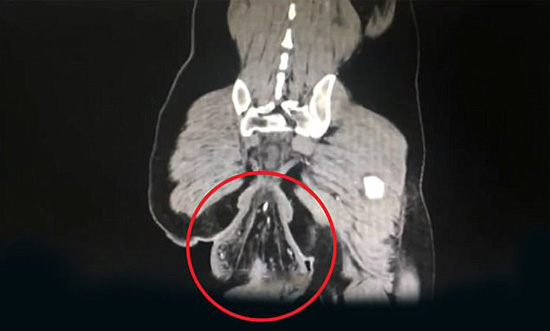

Bilgisayarlı tomografi (BT) taraması, hastanın anüsünün dışında top şeklinde bir çıkıntı gösterdi. Topağın çapı 16 cm (6.3 inç) idi. Dr Su, hastanın bağırsak duvarında çürükler ve kan lekeleri olduğunu da söyledi.